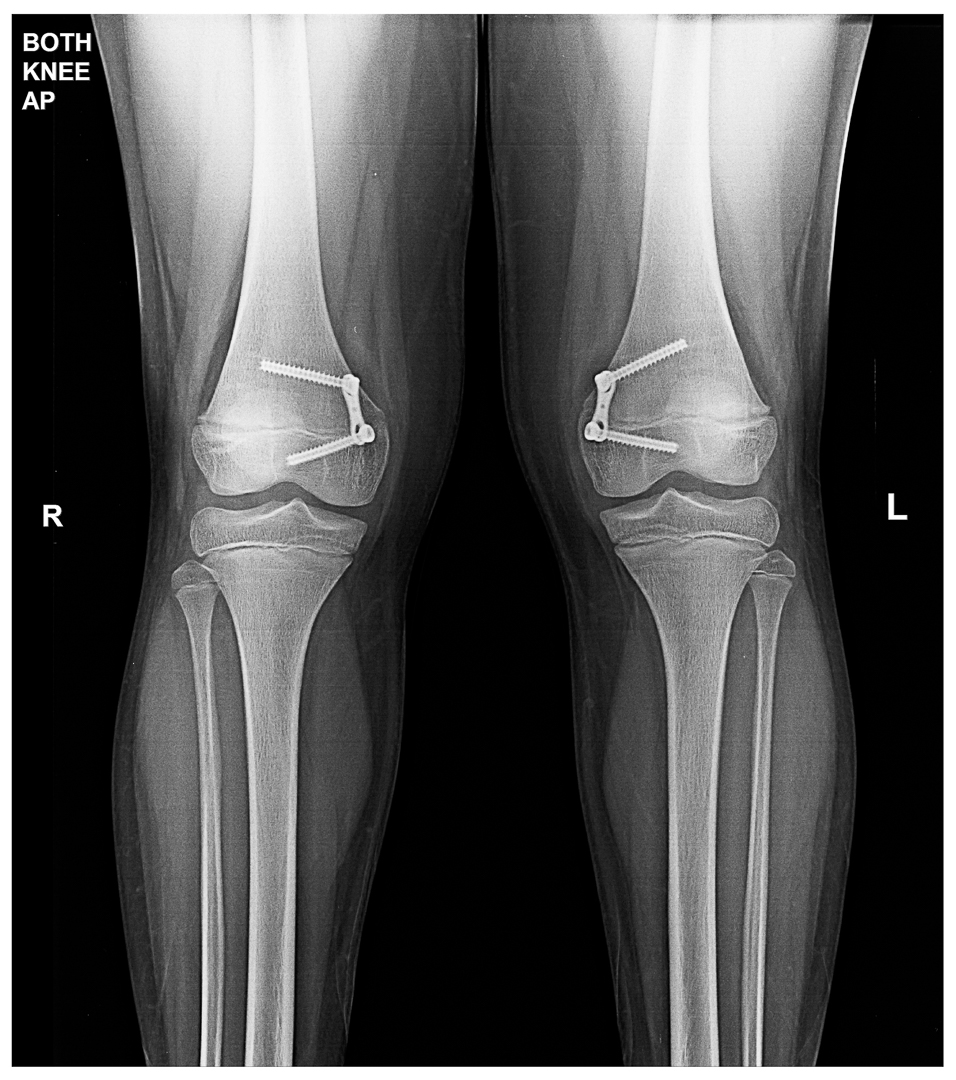

Genu Valgus managed by Growth Modulation:

< 12 year age in female < 13 year in male with sufficient remaining growth :Growth modulation / hemi-physiodesis of distal femur physis / tibia proximal tibial physis (rare)